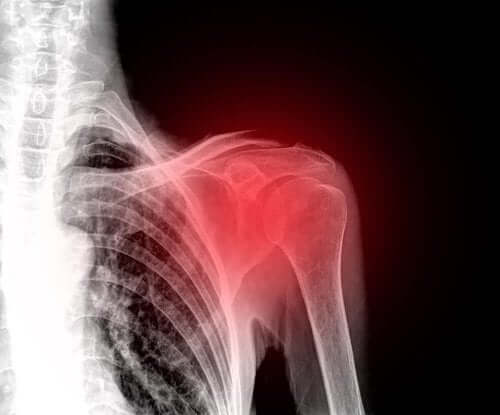

Ρήξη του στροφικού πετάλου του ώμου: Τι πρέπει να γνωρίζετε

Μία ρήξη του στροφικού πετάλου του ώμου είναι ένας τραυματισμός ο οποίος επηρεάζει συχνά τους ώμους σε άτομα μέσης ηλικίας. Έτσι, αποτελεί μία από τις κύριες αιτίες πόνου στους ώμους.

Τα συμπτώματα εξαρτώνται από τη σοβαρότητα του τραυματισμού. Όμως, το κυρίαρχο σύμπτωμα είναι ο πόνος στον ώμο. Ομοίως, περιορίζονται όλες οι κινήσεις αυτής της άρθρωσης.